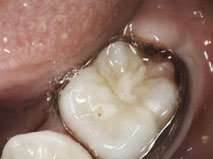

The CO2 laser is also an excellent tool to remove the excess soft tissue. Many pediatric patients require banding of molars, but an overlying operculum gets in the way of placing appliances on these teeth. Figure 6 presents the LightScalpel LS-1005 CO2 laser operculectomy (3 watts SuperPulse Repeat Mode F1-7) prior to band placement. Tissue hemostasis allows for banding to happen immediately after CO2 laser procedure – bands were seated shortly after operculectomy was performed, in the same visit. A local anesthetic may be required in some cases.